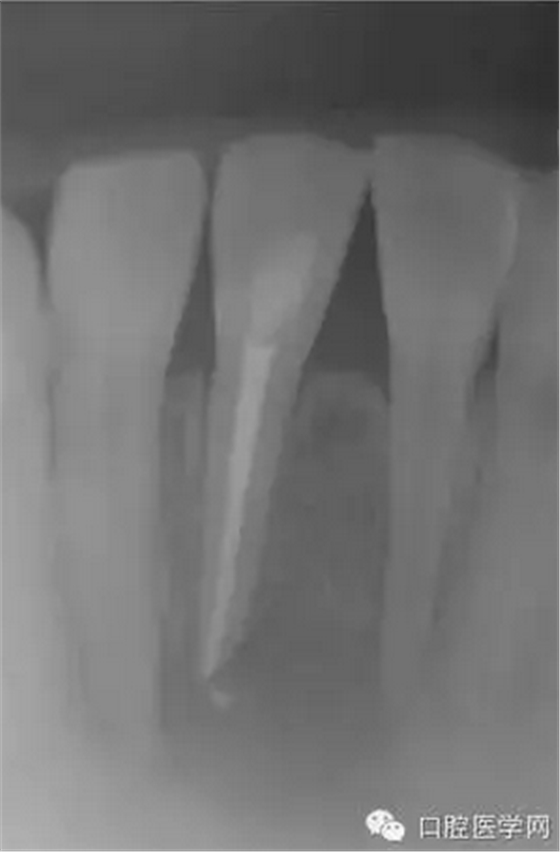

(圖 3) 根管充填

2天后讓患者復(fù)診,查看根管狀態(tài),發(fā)現(xiàn)根管內(nèi)依然有膿液流出,用注射器和針管將根管內(nèi)的膿液吸出來,使用生理鹽水清洗根管后,再用棉球?qū)⒏芊夂谩?天后復(fù)診時(shí),根管狀態(tài)大有好轉(zhuǎn),用NaOCl溶液清洗根管后,為防止根管污染,開髓口使用氧化鋅密封。第10天,切口部位基本痊愈,腫脹也完全消失。此后每隔1~2周復(fù)診一次,使用NaOCl溶液清洗根管,根管內(nèi)填充水溶性氫氧化鈣糊劑。從開始治療算起,約2個(gè)月后,不再有癥狀,進(jìn)行根管充填。